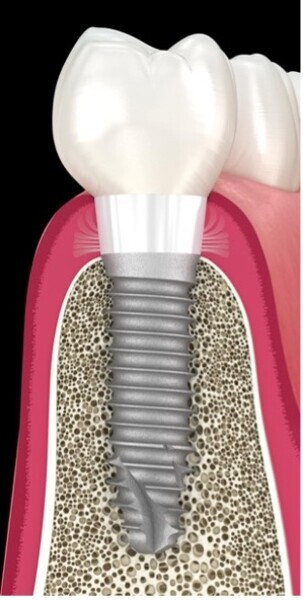

Le succès implantaire à court terme est matérialisé par la bonne intégration tissulaire des implants et notamment L’ostéointégration, il est le fruit d’un concept global de bonne pratique clinique. En revanche, à long terme, des problèmes bio-physico-chimiques auxquels sont soumis les implants dans la cavité orale, peuvent constituer des facteurs de risques qui ont été ignorés, ou négligés, mais qui ont leur importance dans le succès de nos restaurations implantaires. L’inflammation péri implantaire et l’électrogalvanisme7 sont des facteurs de risques qui peuvent contribuer à la corrosion des implants dentaires métalliques et compromettre leur pronostic (Fig. 1).

Fig. 1 : La biocorrosion des implants et des couronnes sur base métallique. L’électro-galvanisme un réel facteur de risque pour le pronostic des restaurations dentaires.

Prendre conscience de ces problèmes de corrosion et bien les connaître peut être une des clés dans la stratégie de lutte contre les péri-implantites.